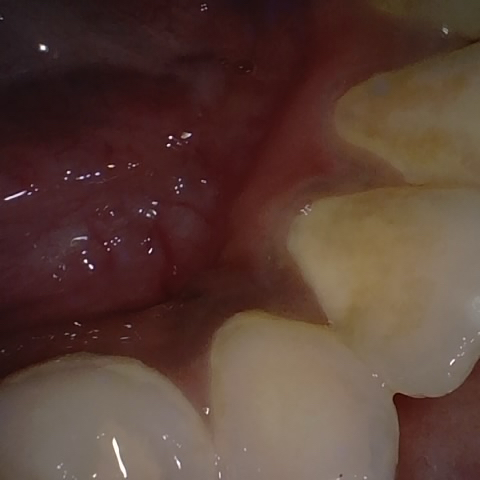

Annotated as "Good"